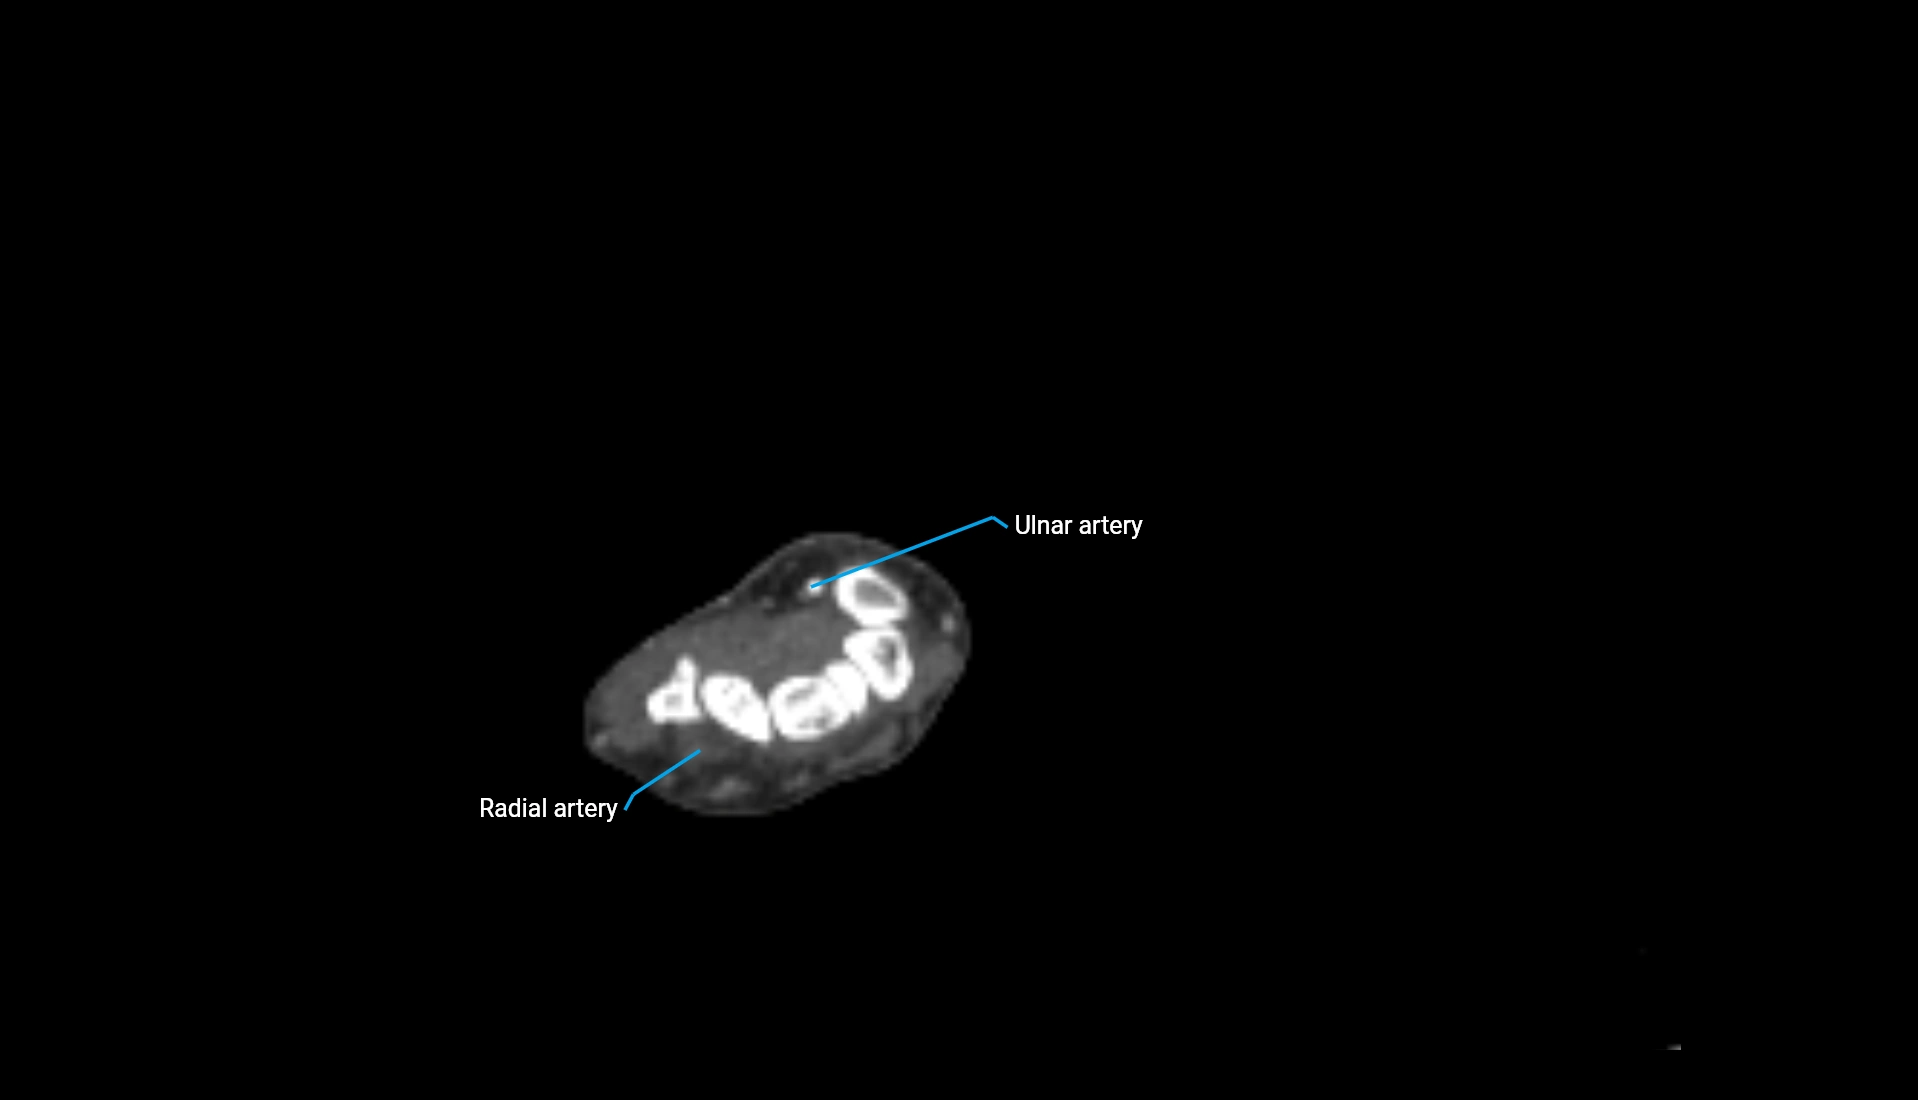

CT Appearance

Non-Contrast CT:

• Cortex: High-density, sharply defined

• Subchondral bone: Dense cancellous matrix

• Articular surface: Smooth concave contour articulating with the capitellum

• Excellent for evaluating bone integrity, alignment, and subtle fractures